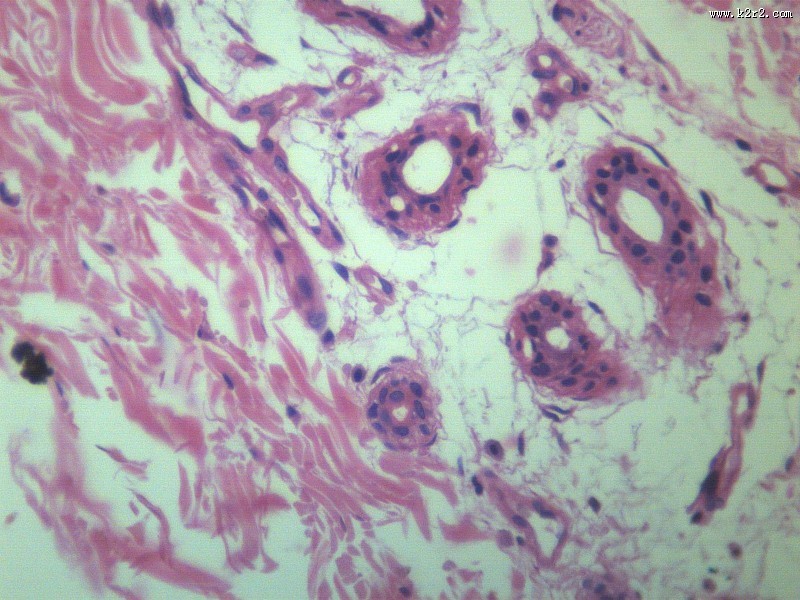

乳头状瘤 - 第12张

乳头状瘤

图集中 / 共有 12 张图片

papilloma of papilla